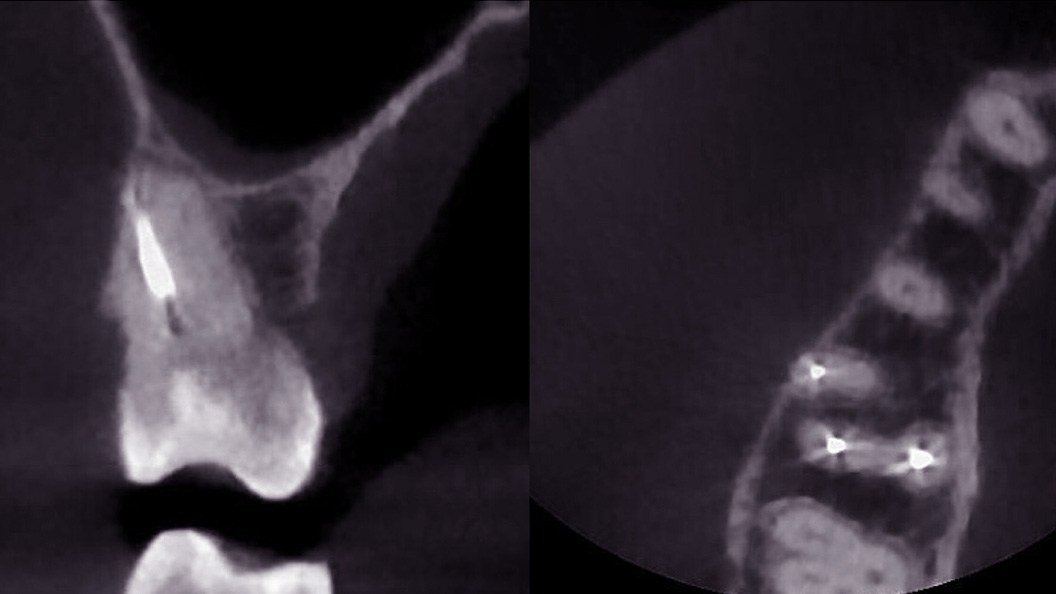

Пациентка после лечения в другой клинике обратилась в «Стоматологию Комфорта» с жалобами на ноющие боли в области жевательных зубов верхней челюсти. Боли усиливались при принятии пищи и горячих напитков. В результате проведения конусно-лучевой компьютерной томографии врач Вахлюева Елена Сергеевна обнаружила пропущенный дополнительный канал в ранее леченом моляре. Проведено селективное эндодонтическое лечение с пломбированием зуба.

- проведение конусно-лучевой компьютерной томографии и выявление проблемы;

- селективное эндодонтическое лечение зуба 1.6;